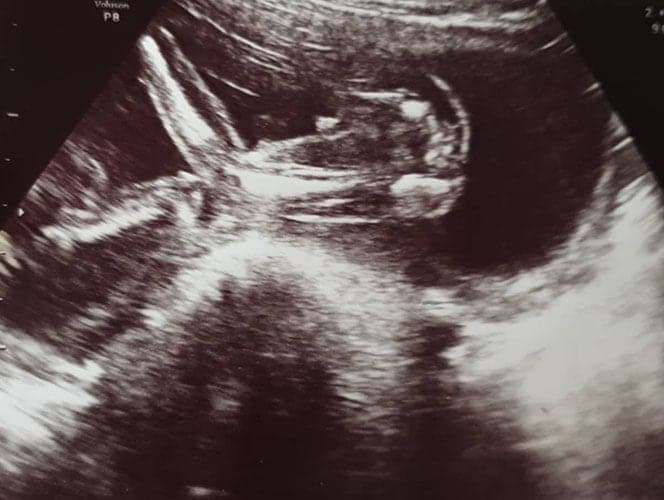

Ultraschallbilder aus dem 1. Trimester (1. SSW bis 12. SSW)

Im ersten Trimester sind die Ultraschallbilder meist noch schwer zu deuten. Oft erkennt man in den letzen Wochen des ersten Trimesters gut den Körper, den Kopf und die Gliedmaße. Das Geschlecht kann man in dieser Zeit meist noch nicht erkennen.